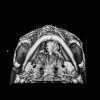

Pemeriksaan radiologi berupa computed tomography (CT) scan dapat dipertimbangkan pada pasien dengan cedera otak traumatik risiko tinggi. Namun, ada kekhawatiran mengenai paparan radiasi pengion dari CT scan terhadap bayi, sehingga beragam metode prediksi lain telah dikembangkan. Artikel ini akan membahas metode penilaian risiko cedera otak traumatik pada bayi dan aplikasinya dalam praktik klinis.[1-3]

Dalam suatu analisis retrospektif, Abid et al. mempelajari akurasi metode PECARN untuk mengidentifikasi bayi usia <3 bulan yang berisiko rendah terhadap COT yang signifikan secara klinis. Dari 1.081 partisipan yang memenuhi kriteria inklusi, sebanyak 70% (750/1.081) mengalami cedera akibat jatuh dan 59% (633/1.081) menjalani CT.

Dari 514 partisipan (47,5%) yang memenuhi kriteria skor PECARN risiko rendah, 0,2% pasien mengalami COT yang signifikan secara klinis, 5,1% mengalami COT dalam gambaran CT scan, dan 4,6% mengalami fraktur tulang kepala.

Di sisi lain, dari 567 partisipan yang tidak memenuhi kriteria PECARN risiko rendah, sebanyak 4,2% mengalami COT secara klinis, 21,3% menunjukkan COT pada CT scan, dan 28% pasien mengalami fraktur tulang kepala.

Studi ini menyimpulkan bahwa metode PECARN akurat untuk mengidentifikasi bayi usia <3 bulan yang berisiko rendah mengalami COT yang bermakna secara klinis. Namun, bayi dengan risiko rendah COT yang bermakna secara klinis mungkin saja menunjukkan gambaran COT di CT scan (tingkat kejadian >5%).

Oleh karena itu, klinisi perlu tetap waspada. Bila bayi tidak memenuhi kriteria risiko rendah PECARN, maka CT scan sangat dianjurkan.[3]